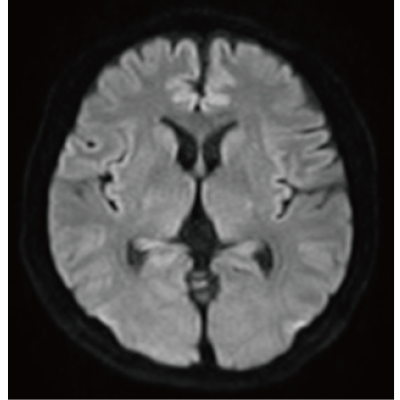

IP-RAPID, que permite um tempo de exame reduzido, mantendo a qualidade da imagem, e DLR Plus, que melhora a qualidade da imagem utilizando a tecnologia Deep Learning*8.

Ao combinar estas duas tecnologias, as imagens de fácil diagnóstico podem ser obtidas com uma velocidade de exame rápida.

O IP-RAPID x DLR Plus também pode encurtar o tempo de aquisição de imagens, permitindo que mais imagens sejam obtidas no mesmo tempo de exame. Imagens adicionais, como diferentes tipos de imagem e seções transversais, podem ser adicionadas ao exame convencional para aumentar a quantidade de informações e tornar o diagnóstico mais fiável.

O IP-RAPID x DLR Plus pode ser usado para exames de imagem básicos, como VolumeScan, RadialScan, HalfScan e muitos outros métodos de imagem, como MultiContrastScan FatSep e DWI.

Também pode ser utilizado com exames demorados, como DWI de corpo inteiro e exames de imagem de toda a coluna, fornecendo informações mais detalhadas em muito mais áreas do que era anteriormente possível.